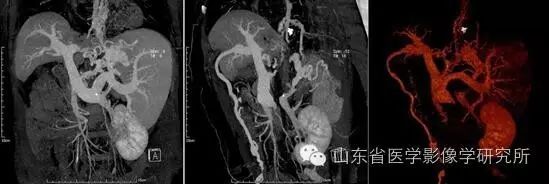

▲患者,62岁,女性,肝硬化、脾肿大、门静脉高压、侧支循环广泛。 MIP和VR技术可以清晰显示食管-胃底-脾门静脉曲张、脾肾静脉分流、脐静脉开口等所有侧支循环通路。

▲患者为34岁男性,左手拇指和食指受伤,正在接受左手CTA检查。 VR三维成像技术可以清晰显示掌浅弓、掌深弓以及拇指和食指固有动脉,为制定手术方案提供准确、直观的依据。

▲ 患者是一名 40 岁男性,患有左肾上极肾癌。 MIP、VR三维、伪彩技术可以清晰直观地显示肿瘤的供血动脉,增加了实施保肾肿瘤剜除术的信心。